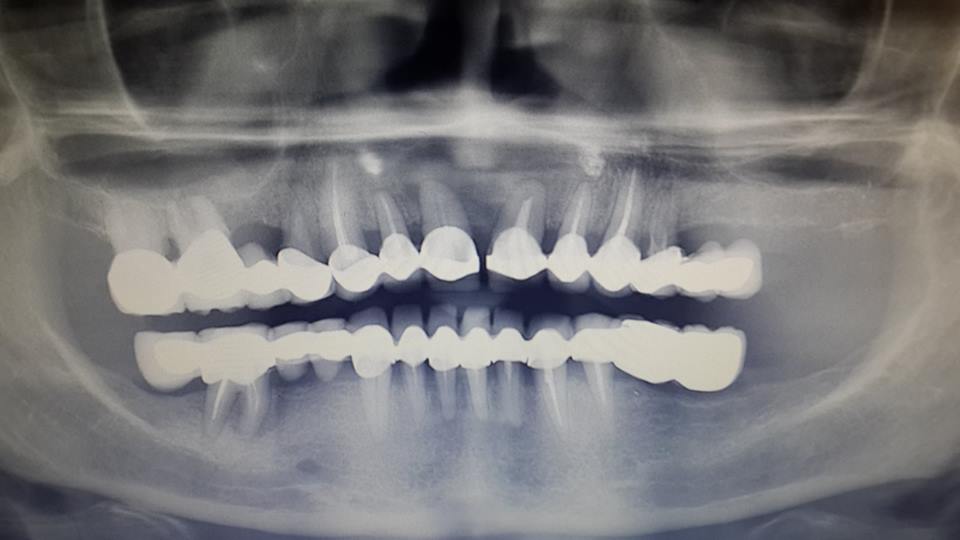

An example of complete rehabilitation of the oral cavity. Treatment included the removal of the old prosthesis, treatment of paradontitis, removal of a large cyst, implantation, clasp prosthesis.